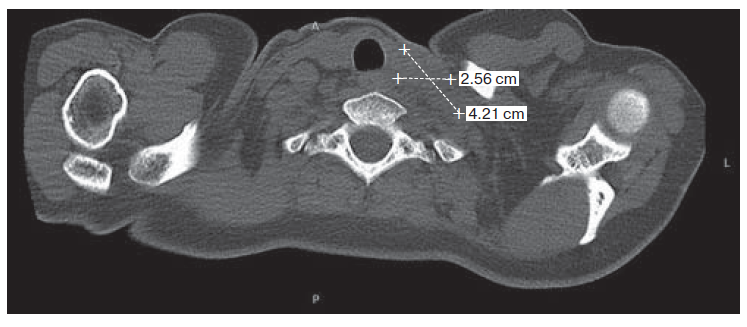

4. Fig. 3. Magnetic resonance tomogram of soft Neck tissue and computer tomogram of organs thoracic cavity.

View (728KB)

6. Fig. 5. Magnetic resonance tomogram of soft tissues of the neck: in the upper mediastinum on the left two nodal formations, merging with each other, in size 25 × 15 mm and 25 × 19 mm, involving the pre-invertebrate cellulose. On the right in the lower third of the neck is a conglomerate altered lymph nodes measuring 42 × × 28 × 34 mm, growing to adventitious carotid Artery and to the anterior wall of the jugular vein.

View (551KB)